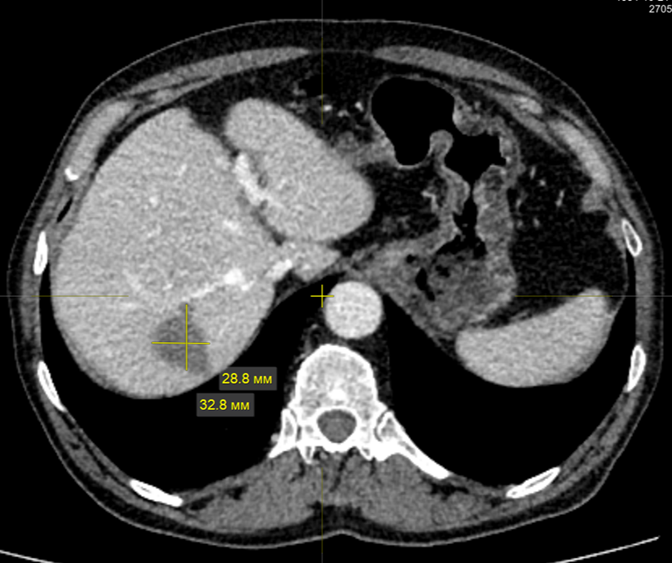

3. Рис. 3. КТ от 27.05.24. В S7 печени определяется образование с нечеткими неровными контурами, размерами 28,8×32,8 мм. Частичный ответ. Примечание: рисунок выполнен авторами | |